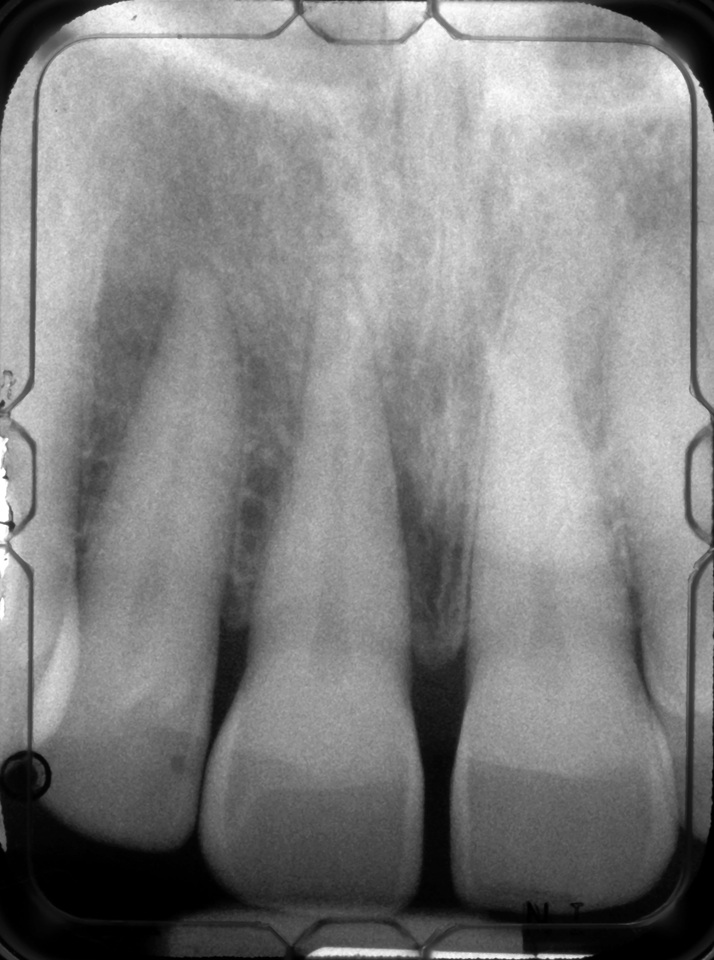

Facial bone loss and a mesial vertical defect.

Fig. 3